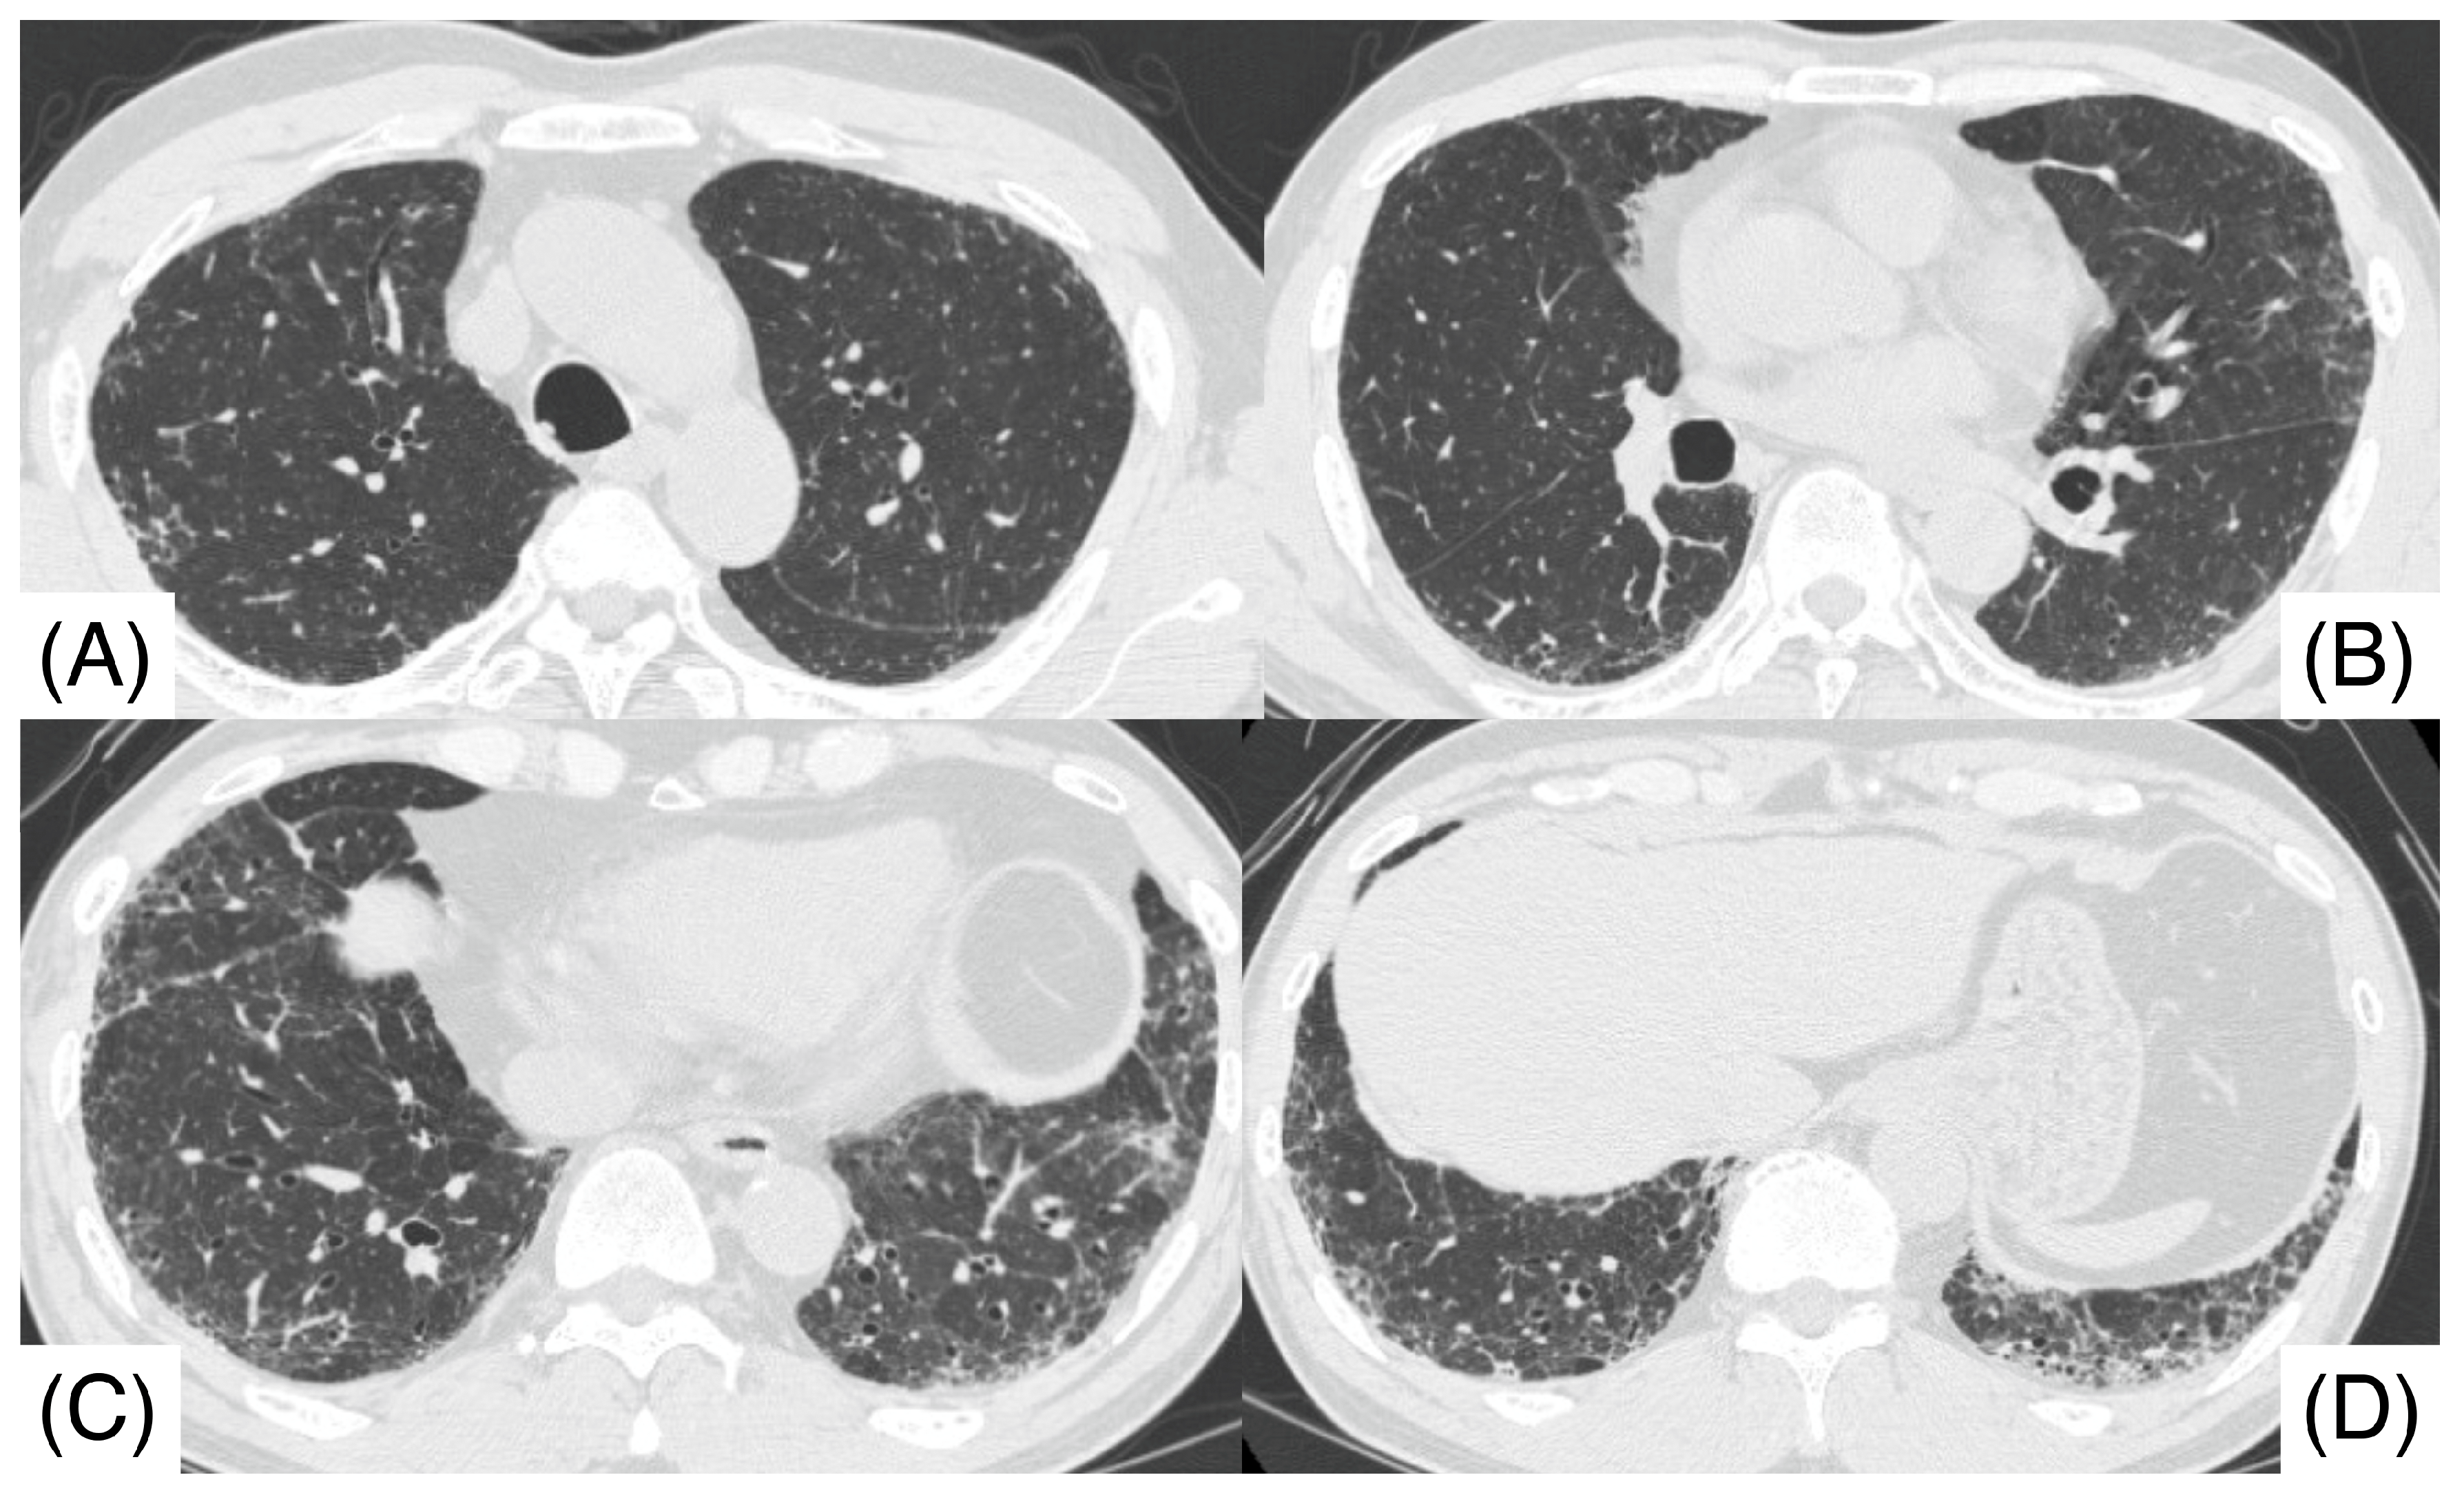

2. Case Report